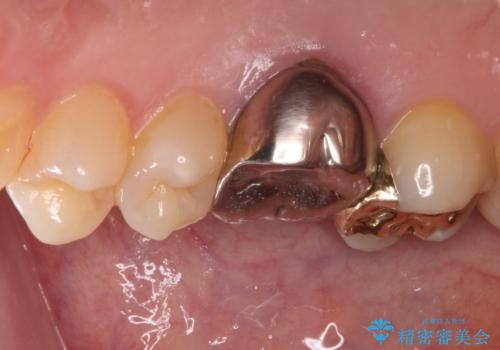

穴の空いてしまった奥歯 ゴールドインレーによるむし歯治療

- 奥歯にものが挟まって痛みがあるとのことで来院された患者様です。

目視でも分かるくらいの欠損があり、歯の内部にむし歯が進行している状態でした。

上顎奥歯で目立たないことから、ゴールドインレー(PGAインレー)による修復治療をおこなうこととしました。

ゴールドインレーは銀歯のインレーやセラミックインレーと比べ、「技工操作の精度が高く、適合が著しく良い」というメリットがあります。特に上の奥歯は歯科医師の操作が行いにくいため、「適合の良さ」は再治療のリスクを防ぐ上でとても重要な要素となります。

上の奥歯は金属色が見えることもないため、審美的な問題は全くありません。